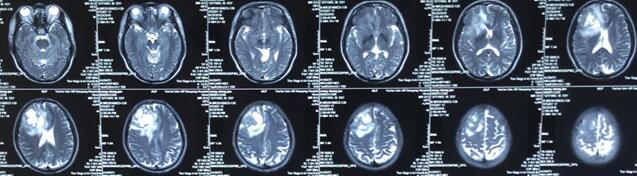

患者王某某,男,53岁,因“间断头痛半月”入神经内科十二病区,发现颅内占位后转入神经外科。既往患者有肺Ca病史,于一年前行手术治疗。头颅影像学诊断胶质瘤?转移瘤待排。2016年6月29日在3.0T磁共振定位后,刘增强副主任与其团队为患者实施了立体定向脑内病变活检术,此患者病灶为囊实性,手术难度较大,而一旦囊液流失则会发生脑组织漂移,导致靶点移位,因此手术计划制定尤为重要,入颅点为右额部,穿刺后首先达到肿瘤实性部分,获取病灶标本后,抽出部分囊液以缓解患者高颅压症状,经过精细的手术操作,最终成功获取肿瘤标本,并且抽出约20ml肿瘤液,患者情况稳定,术后两小时即下床活动。

术后冰冻切片报告考虑转移瘤,我院石蜡病理结果为少许低分化癌组织,结合病史符合肺癌脑转移。